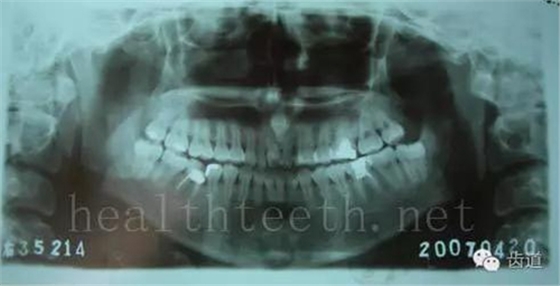

掌跖角化-牙周破壞綜合征(一種家族遺傳病在牙周的表現(xiàn))